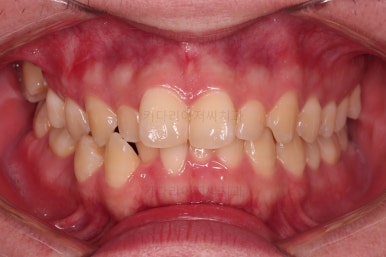

부산교정치과 초진 시 입안의 모습입니다.

앞니가 삐뚤어서 결손치아가 없었더라도 교정치료를 원하셨던 상황이었고요.

오른쪽 어금니 맞물림은 결손치아도 그렇지만 전반적인 앞뒤 차이가 있는 부정교합이 있었어요.

치료계획을 세울 때, 단순히 결손치아만을 고려하는 것이 아니라 얼굴모습, 중앙선, 다른 치열의 삐뚤어진 상태, 교합 등을 고려해서 계획을 세웁니다.

이번 환자분은 부정교합 부분은 발치 없이 치열을 통째로 뒤로 밀어서 개선하기로 했고요.

결손치아 부위는 더 뒤의 어금니와 사랑니까지 앞으로 당겨와서 임플란트 없이 공간을 모아주기로 했어요.